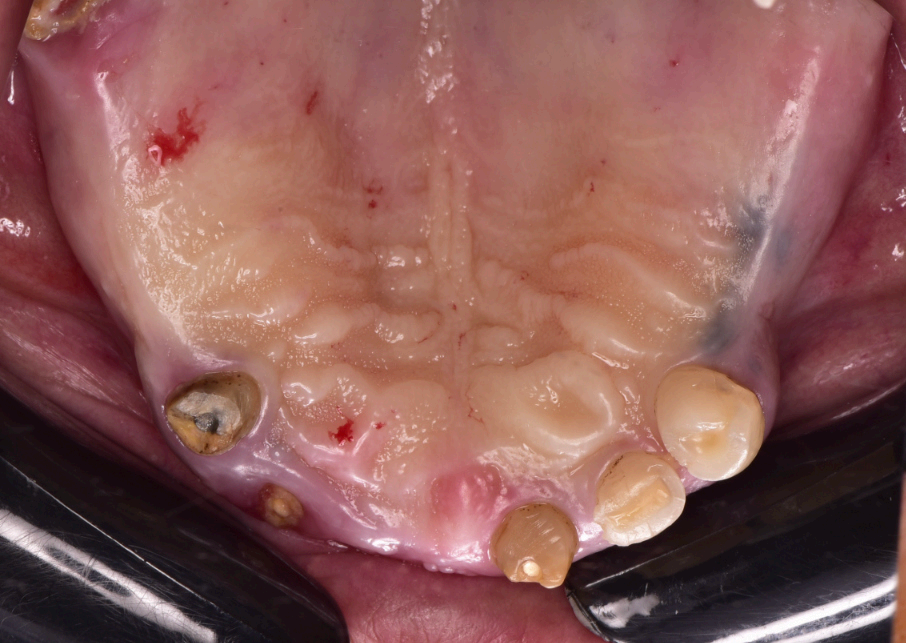

Preoperative and Planning •Fig. 1.1: Frontal intraoral view of the maxilla showing residual roots and fractured teeth. •Fig. 1.2: Occlusal intraoral view highlighting the compromised dentition. •Fig. 1.3: Digital wax-up integrated with a 3D facial scan and smile design guidelines. •Fig. 1.4, 1.5: Visualization of implant positions (16, 14, 12, 22, 24, 26) on a 3D model, prosthetically driven placement. •Fig. 1.6: 3D rendering of the wax-up aligned with the bone level, illustrating bone-prosthesis relationship.

The patient, a 70-year-old female, presented to the dental clinic with a chief complaint of compromised maxillary dentition and a desire for a fxed, aesthetically pleasing rehabilitation. Her medical history was unremarkable, with no systemic diseases, allergies, or medications reported, and her general health was deemed excellent for her age. Intraoral examination revealed a partially edentulous maxilla with failing dentition: residual roots were present at positions 13 (upper right canine) and 21 (upper left central incisor), while teeth 22 (upper left lateral incisor) and 13 exhibited fractures rendering them non-restorable (Fig. 1.1, 1.2). The patient expressed a strong preference for a fxed prosthesis that would restore both function and aesthetics, with a natural gingival contour as a priority.

Initial diagnostic workup included a comprehensive radiographic evaluation using cone-beam computed tomography (CBCT) to assess bone volume and quality at the proposed implant sites: 16 (upper right frst molar), 14 (upper right frst premolar), 12 (upper right lateral incisor), 22 (upper left lateral incisor), 24 (upper left frst premolar), and 26 (upper left frst molar). The CBCT confrmed suffcient bone height and width to support six implants without the need for extensive grafting, though minor bone leveling was anticipated. Digital impressions were acquired using the Shining3D Elite intraoral scanner, capturing detailed surface anatomy of the maxilla and remaining teeth. A 3D facial scan was also performed to integrate smile design principles, ensuring the prosthetic outcome aligned with the patient’s facial aesthetics (Fig. 1.3). A digital wax-up was created in Exocad, simulating the fnal prosthesis with attention to tooth proportions, midline alignment, and lip support. After patient approval, this wax-up served as the foundation for implant planning (Fig. 1.4, 1.5).